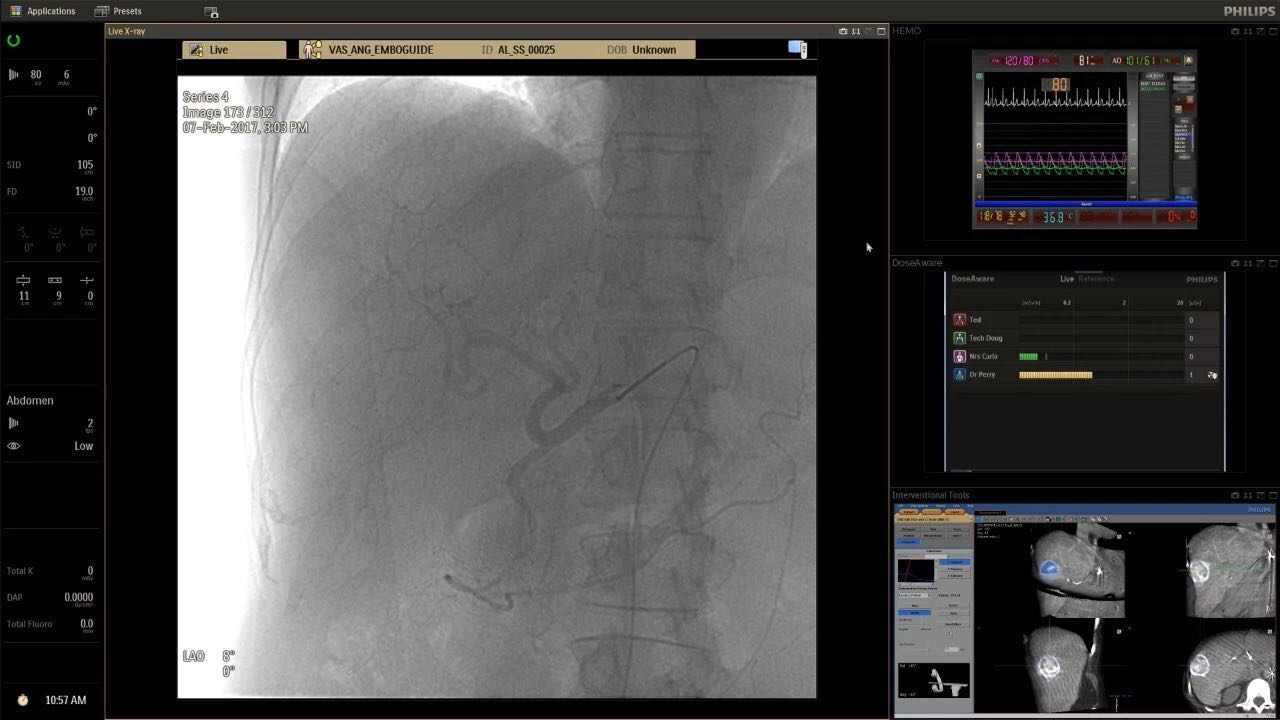

在日益復(fù)雜的干預(yù)期間,臨床醫(yī)生需要快速、輕松地可視化關(guān)鍵解剖結(jié)構(gòu)并確定手術(shù)過(guò)程中患者的變化。2019年1月17日,飛利浦宣布推出采用FlexArm的Azurion 7 C20,旨在提高圖像引導(dǎo)程序的定位靈活性。

帶有FlexArm的Azurion 7 C20 包含一系列創(chuàng)新技術(shù),使臨床醫(yī)生可以更輕松地在整個(gè)患者身上進(jìn)行二維和三維成像。當(dāng)臨床醫(yī)生移動(dòng)系統(tǒng)時(shí),圖像光束自動(dòng)保持與患者的對(duì)準(zhǔn),允許更一致的可視化并使他們能夠?qū)⒆⒁饬性谥委熒稀?/span>

(FlexArm C型臂可以沿著工作臺(tái)的兩側(cè)提供偏心成像。這允許醫(yī)生在左臂或右臂上進(jìn)行徑向進(jìn)入病例,完全或部分伸展,而無(wú)需移動(dòng)患者或樞轉(zhuǎn)桌子。X射線束與手臂保持對(duì)齊,以促進(jìn)其整個(gè)長(zhǎng)度的平滑導(dǎo)航,而無(wú)需進(jìn)行持續(xù)調(diào)整。)

飛利浦表示,采用FlexArm設(shè)計(jì)的Azurion 7 C20可提供卓越的靈活性和直觀的控制。該系統(tǒng)由智能運(yùn)動(dòng)引擎驅(qū)動(dòng),可在八個(gè)不同的軸上移動(dòng),所有這些軸均由其單個(gè)“Axsys”控制器控制。臨床醫(yī)生的模擬測(cè)試表明,該系統(tǒng)有可能顯著減少患者,工作人員和設(shè)備的重新定位,從而改善微創(chuàng)手術(shù)的可及性,包括通過(guò)患者手腕進(jìn)入身體的手術(shù)(橈動(dòng)脈入路),并降低患者的風(fēng)險(xiǎn)。無(wú)意中拔出電線和管子,以及節(jié)省大量時(shí)間。該系統(tǒng)非常適合混合手術(shù)室(OR),可滿足一個(gè)房間內(nèi)的多種專業(yè)需求,例如手術(shù)和血管內(nèi)手術(shù)的組合。

FlexArm在不少于8軸的情況下旋轉(zhuǎn),從而創(chuàng)建幾乎無(wú)限的靈活性來(lái)執(zhí)行成像,從頭部到腳部在左側(cè)和右側(cè)進(jìn)行2D和3D可視化。圖像光束保持與患者對(duì)齊,允許在旋轉(zhuǎn)或角度期間更好地可視化解剖結(jié)構(gòu)。使用Axsys運(yùn)動(dòng)控制系統(tǒng)輕松操作支架。